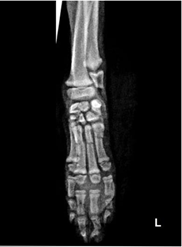

The animal was admitted for further diagnostic investigations and pain management. Emergency pain management included the administration of carprofen (Rimadyl; Zoetis) 4mg/kg as a single subcutaneous injection. The animal was prepared for general anaesthesia in order to acquire radiographs of the affected limp. Anaesthetic premedication included the administration of xylazine (Rompun; Bayer) 1mg/kg intramuscular injection in conjunction with atropine (Atropine Sulfate; Bradex) 0.01mg/kg intramuscular injection. Induction was achieved with propofol (PropoFlo; Zoetis) 2mg/kg administered intravenously in a bolus rate. Anaesthesia was maintained with a mixture of isoflurane (IsoFlo; Abbott) 1.5% with 20% oxygen in a constant inhalation rate administered via a cuffed endotracheal tube throughout. One lateral (LT) and one dorsopalmar (DP) radiograph of the carpo-metacarpal region were acquired, incorporating the distal antebrachium (Photo 1). Radiographs revealed the presence of single transverse shaft fractures of the third (CIII), fourth (CIV) and fifth (CV) carpal bones, located at the proximal second fourth (2/4) of the carpal body in all carpals. A moderate caudo-lateral dislocation of the distal fracture fragments was present in all three carpals. There was also a symphysiolysis of the distal symphysis of the second (CII) carpal bone right above the dorsal sesamoid, with lateral dislocation. Nothing abnormal was detected on the distal antebrachium, the carpus and the phalanges. These findings were deemed consistent with the presence of pain, swelling, abnormal gait, crepitus and valgus and would have resulted directly from an acute forelimb injury as also described by the animal’s history.3‒5

Photo 1 Dorsopaimar (a) and Lateral (b) radiograph of the metacarpais showing the fractures in the yellow circles. Notice the slight valgus of the forelimb evident on the dorsopalmar projection.